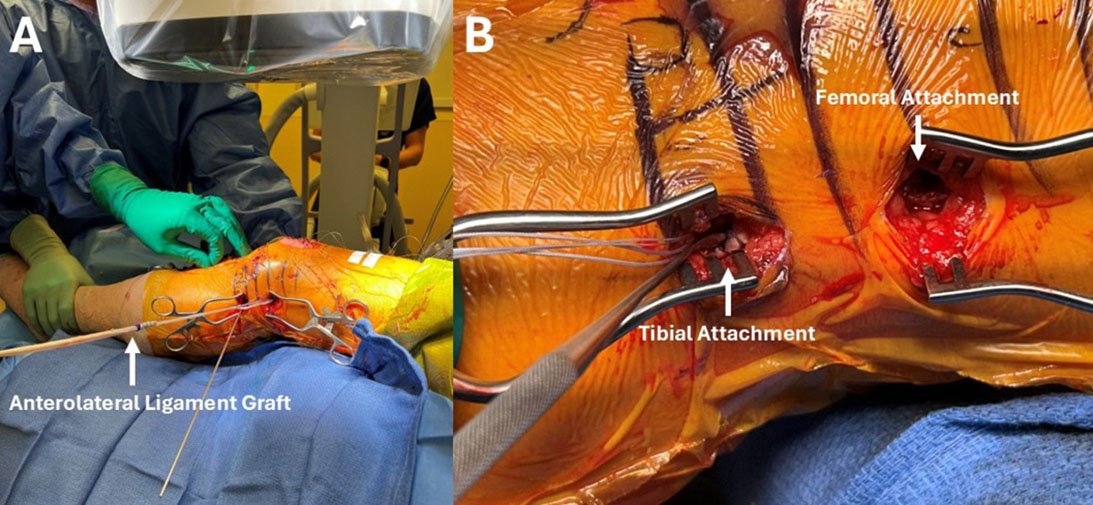

New literature expands on the role of lateral extra-articular procedures for patients needing ACL reconstruction

While the outcome of anterior cruciate ligament (ACL) reconstruction is generally successful, clinical failure, including secondary injury of the ACL graft or excessive laxity of the repaired knee, still occurs with frequency.